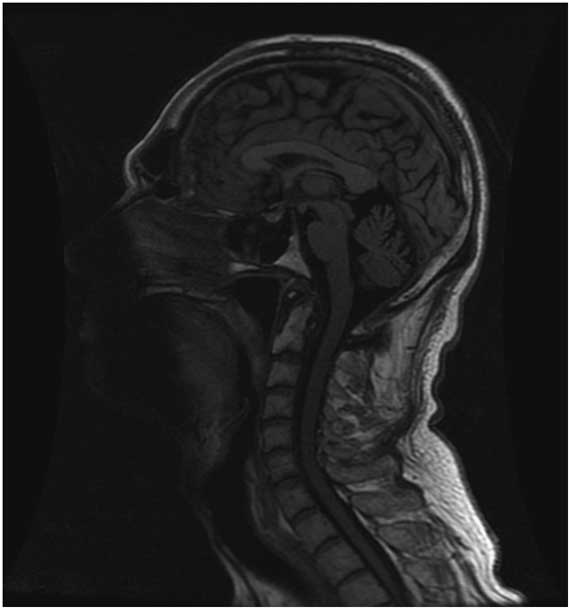

However, repeat CT head suggested worsening SIH with an enlarged left SDH resulting in mild midline shift (Figure 2). A large-volume EBP was performed from spinal levels T2 through S1 to a total volume of 56 ml.Reference Staudt, Pasternak and Sharma 3 After a week, he was free of headache, oriented in all spheres, and had no further hallucinations. However, with the increased left SDH and left-to-right shift, burr hole evacuation was also performed. Upon discharge from the hospital, he remained oriented, with no headache, no psychiatric symptoms, significantly improved cognition (MoCA 29/30) and stable gait. At 3-month follow-up, the patient was headache-free, his chorea was at baseline, he was driving and had resumed work. MoCA was 29/30. MRI showed small bilateral SDHs with improved configuration of the midline brain structures and resolution of brain slumping (Figure 3).

Figure 3 T1 sagittal brain MRI at 3-month follow-up showing radiologic improvement of spontaneous intracranial hypotension including improvement of the configuration of the brain midline structures, decreased downward displacement of the brainstem and less supratentorial parenchymal slumping.